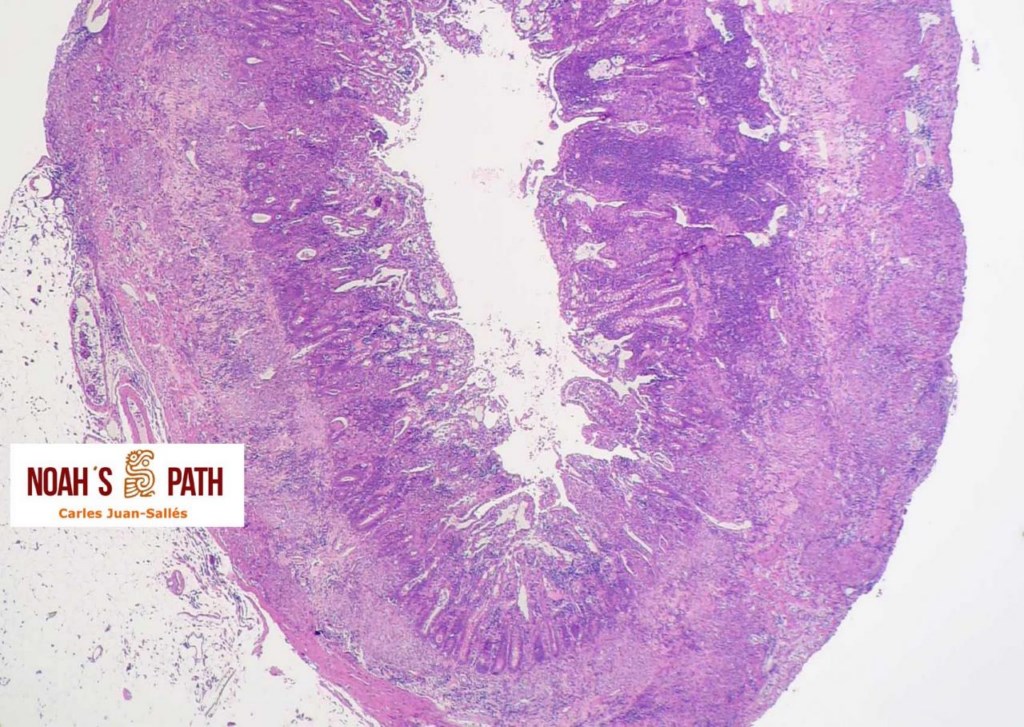

Encabezando uno de los dos grupos españoles que caracterizaron por primera vez la infección por coronavirus sistémico en hurones domésticos en 2004-2006, enfermedad que representa todavía una causa de mortalidad mayor en esta especie; en este estudio se colaboró con diversas Instituciones en Alemania y EUA para la demostración de antígeno en las lesiones y caracterización genómica parcial del agente. Garner MM, Ramsell K, Morera N, Juan-Sallés C, et al: Clinicopathologic features of a coronavirus-associated disease resembling feline infectious peritonitis in the domestic ferret (Mustela putorius). Veterinary Pathology 45:236-46, 2008.